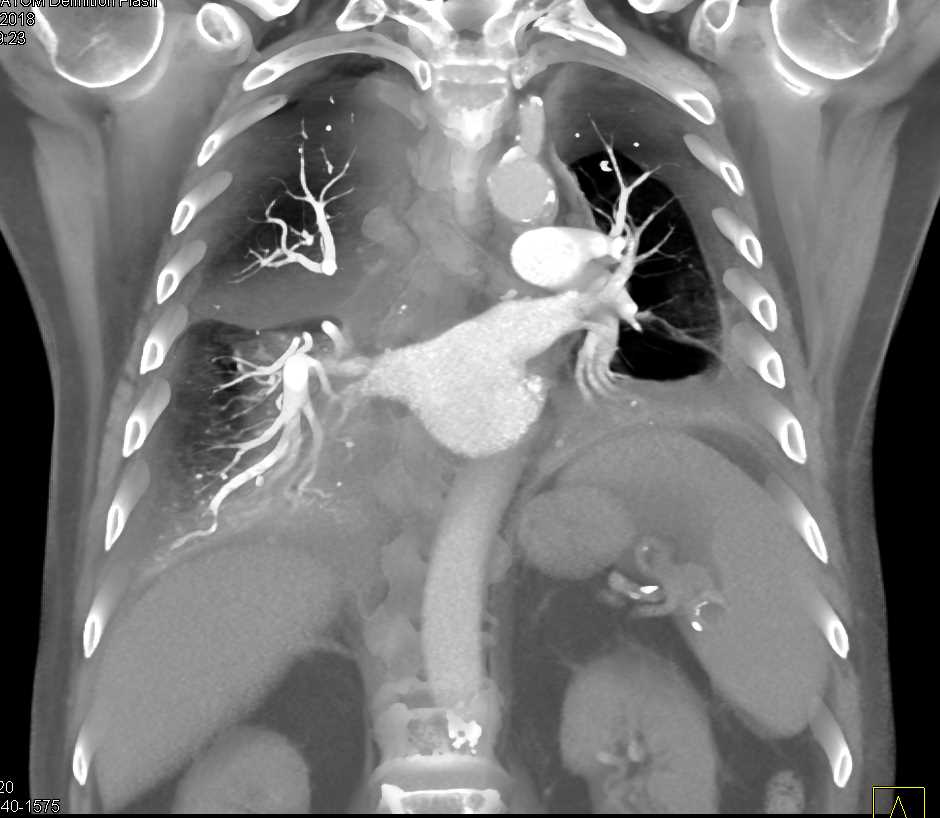

Diagnosis

Post Cardiac Surgery Changes